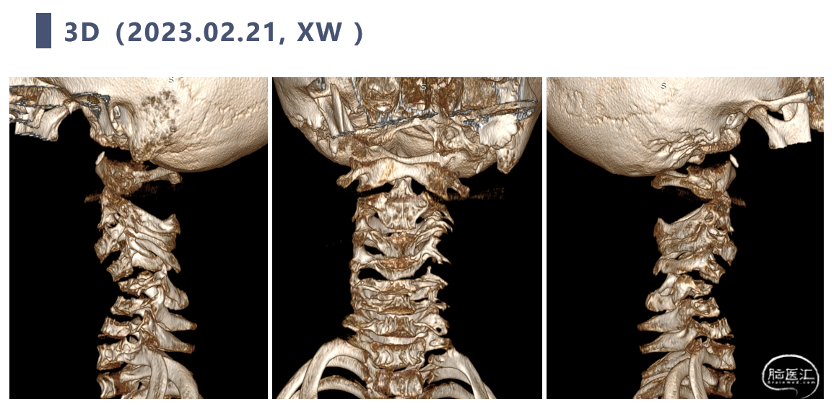

CT

CT显示颈椎椎体最大深度只有8mm,枢椎椎弓根直径3.2mm